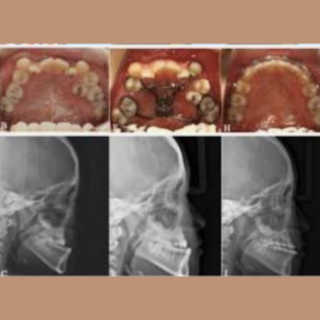

Maxillary hypoplasia is a condition characterized by the underdevelopment of the upper jaw (maxilla), which can affect both facial appearance and oral function. It often results in a sunken midface, improper bite alignment, and may contribute to breathing or speech difficulties. This condition can be congenital or develop during growth, impacting overall facial harmony and balance.

- Pre-surgical Orthodontics: Often needed before the actual surgery takes place. Imaging: X-rays and CT scans are required.

- Planning: Virtual surgical planning is performed on a computer, along with model surgery.